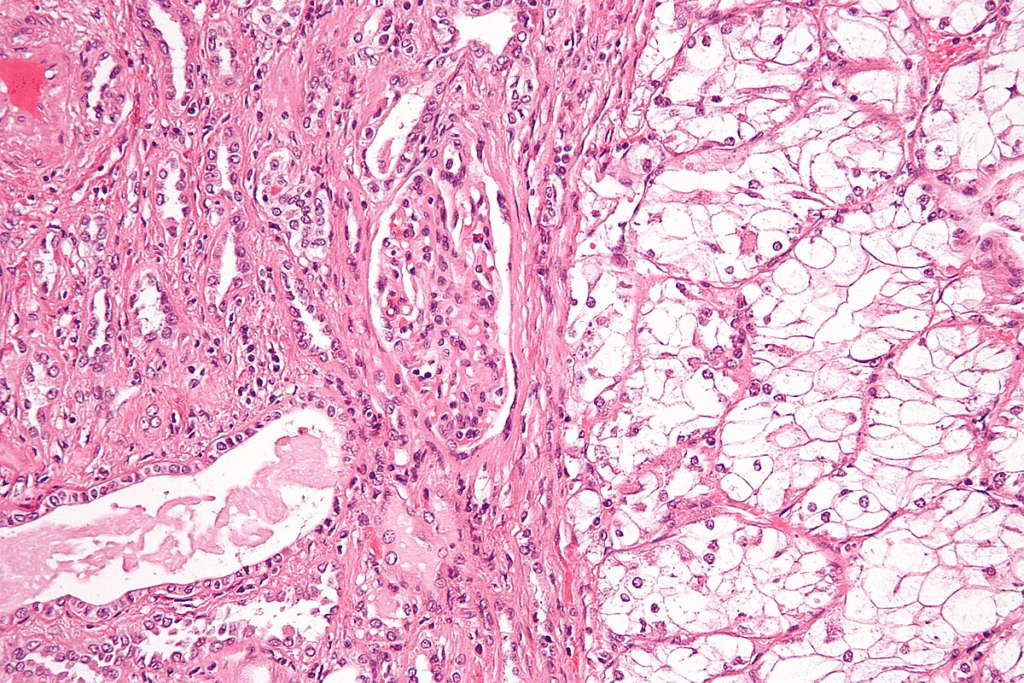

Solid tumors are grouped by where they start and how they look under a microscope. The main types are:

Carcinomas, which start in epithelial cells, are the most common. Examples are breast, lung, and colon cancers. Sarcomasstart in connective or muscular tissues. Gliomas, from the brain’s glial cells, are another big group.